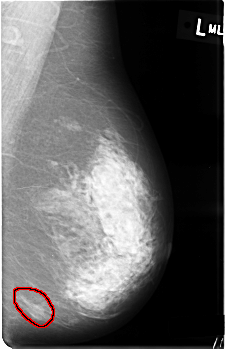

C_0362_1.LEFT_MLO

LEFT_MLO LINES 4528 PIXELS_PER_LINE 2920 BITS_PER_PIXEL 12 RESOLUTION 50 OVERLAY

FILE: C_0362_1.LEFT_MLO.OVERLAY

TOTAL_ABNORMALITIES 1

ABNORMALITY 1

LESION_TYPE MASS SHAPE OVAL MARGINS ILL_DEFINED

ASSESSMENT 4

SUBTLETY 5

PATHOLOGY BENIGN

TOTAL_OUTLINES 2